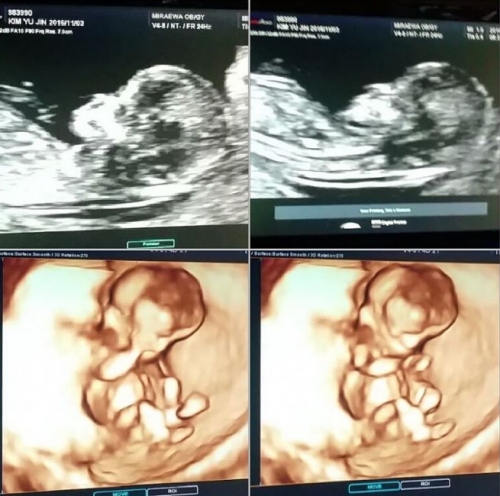

(사진=박준형 인스타그램)

16일 박준형은 자신의 인스타그램에 초음파 사진을 게재하며 아내의 2세 임신 소식을 전했다.

이어 그는 "일단 이 사진은 12주 됐을 때 거고요, 건강하고요. 이제는 14주 좀 넘었어요~ 코랑 이목구비가 뚜렷하고 좀 나 닮은 거 같기는 해요. 내년 봄에 낳으니까 저랑 띠동갑 닭띠네요. 그냥 쭈니는 하느님한테 축복받은애기 감사하고, 여자 애기건 남자 애기건 그냥 건강하기만 하면 고마울 거예요~ 그리고 많이 축하해주신 분들 너무 감사합니다. 땡큐! 빼애앰!"이라면서 감사를 전했다.